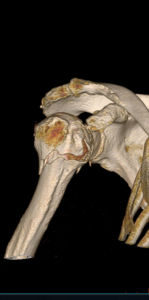

- Shoulder Fractures.